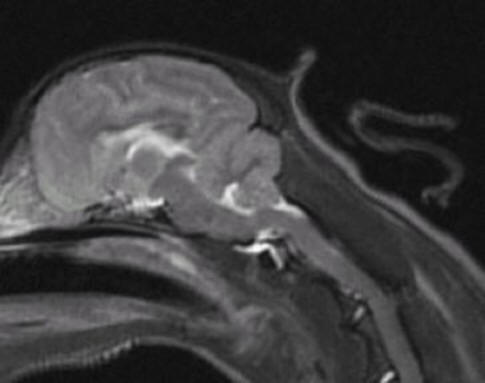

L-about

3 years old R-about 8 years old

No symptoms of SM

Little to no malformation

Little to no herniation of cerebellum

Cerebellums quite full with almost no

pinching/squashing

Medulla almost normal

No syrinxes present